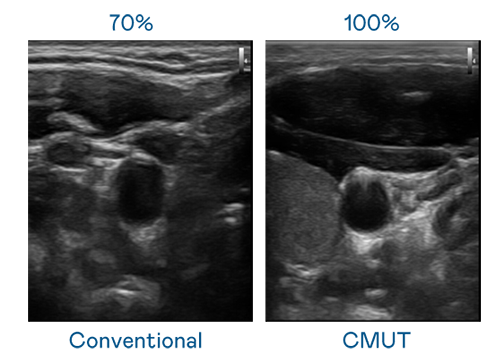

CMUT 技术是一种用电容式微机电元件来产生超音波讯号的技术。与传统 PZT 压电式技术相比,CMUT 频宽增加 30%,更宽频的超音波讯号让影像解析度大幅提升,是实现高影像品质医疗超音波扫描、促进精准医疗发展的关键技术。

超音波影像的解析度高低,首先取决于探头能发出的讯号频宽。BBIN宝盈 CMUT 可提供高清晰的超音波讯号,提供高频宽、高灵敏度、影像纹理细节更高的超音波影像,协助医护人员缩短影像判读时间及利用精准的医疗影像进行诊断。